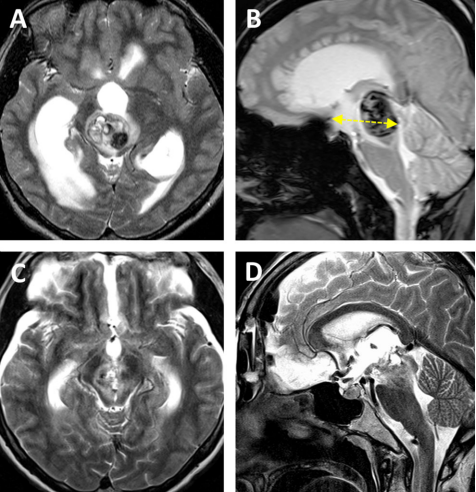

案例1:一名没有既往病史的20岁女性突然出现意识紊乱并逐渐恶化的意识,并出现左偏瘫。MRI显示新鲜海绵状血管瘤典型的中脑轴内出血,连续性急性梗阻性脑积水出血。病变位于腹侧中脑中线,体积为10.7立方毫米,深度为42.5毫米和11.6°的肿瘤侧倾角(图3a,b)。去除双额基底半球间出血性病变放置右外部心室引流后3天,该方法成功完成。

术后病人的恢复也很顺利。患者的意识和偏瘫迅速好转。脑积水消退,不需要分流放置。病人步行出院,没有3个月后随访的神经或认知功能障碍。术后MRI显示完全切除了轴内血肿和血管病变(图3C,D)。

图A和B显示术前MRI影像,被分类为Bcentral病变的出血性中脑海绵状血管瘤。黄色虚线表示肿瘤深度(42.5毫米)。图C、D显示完全清除血管病变后的术后MRI